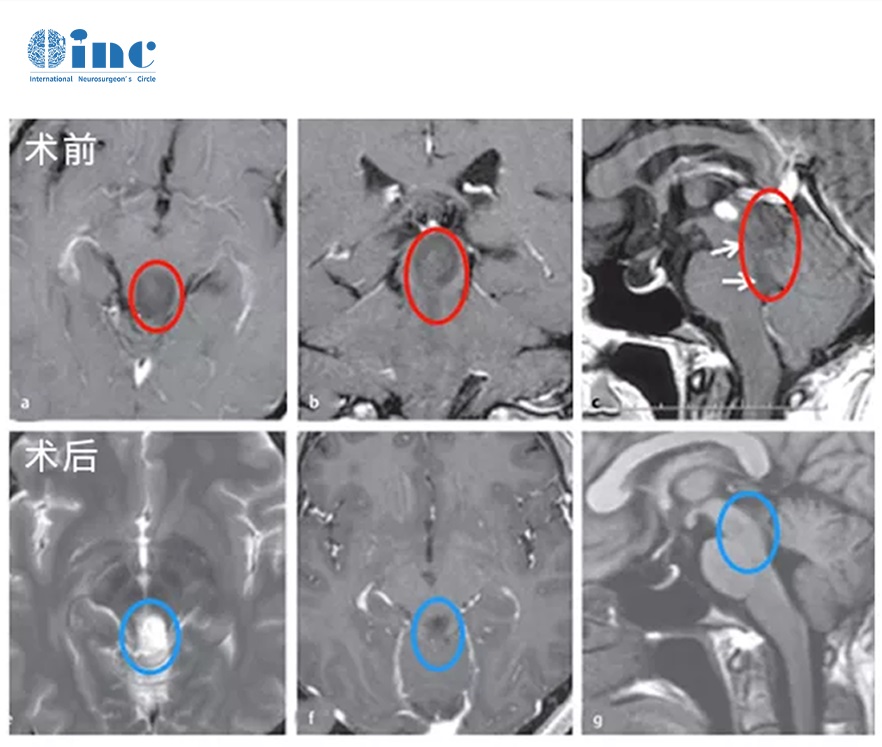

案例2:腦干乳頭狀膠質(zhì)神經(jīng)元腫瘤PGNT

36歲W女士,因中腦頂蓋外生腫瘤引起了阻塞性腦積水,出現(xiàn)嚴(yán)重頭痛及步態(tài)共濟(jì)失調(diào), 地方醫(yī)院建議保守治療,手術(shù)后致癱致殘風(fēng)險(xiǎn)高達(dá)90%以上。于是先在醫(yī)院進(jìn)行腦室腹腔分流術(shù)后癥狀有所緩解,但仍還沒有解決根本病因所在后到德國INI國際神經(jīng)學(xué)研究所請INC巴特朗菲教授主刀手術(shù)獲得全切,患者原有癥狀完全緩解,無新發(fā)癥狀,生活很快恢復(fù)正常。病理結(jié)果為乳頭狀膠質(zhì)神經(jīng)元瘤(PGNT),I級低級別腦干膠質(zhì)瘤。術(shù)后11年隨訪,腫瘤沒有復(fù)發(fā),患者享受正常人的生活。

腦干乳頭狀膠質(zhì)神經(jīng)元腫瘤PGNT